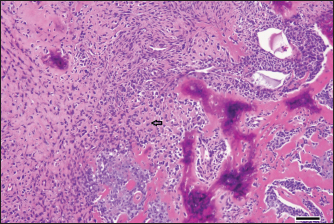

On day 14, the patient underwent surgery to resect the mass lesion. After inducing general anesthesia, the mandibular mass lesion was excised. The resected mass was a large neoplastic lesion in the subcutaneous tissue with extensive necrosis in the center. In the tumor tissue corresponding to the mass wall, bundles, sheets, and wreaths of osteoblast-like tumor cells with bone formation were observed (Fig. 4). These tumor cells were moderately atypical, and numerous mitotic figures were observed. No vascular invasion was observed, and the resection margin was good. Together with the CT scan results, the diagnosis of extraskeletal osteosarcoma was made.

Fig. 4. Histopathological examination results of the resected mass lesion. In the tumor tissue corresponding to the mass wall, bundles, sheets, and wreaths of osteoblast-like tumor cells (arrow) with bone formation were observed. The tumor cells were moderately atypical, and numerous mitotic figures were observed; bar, 100 μm.